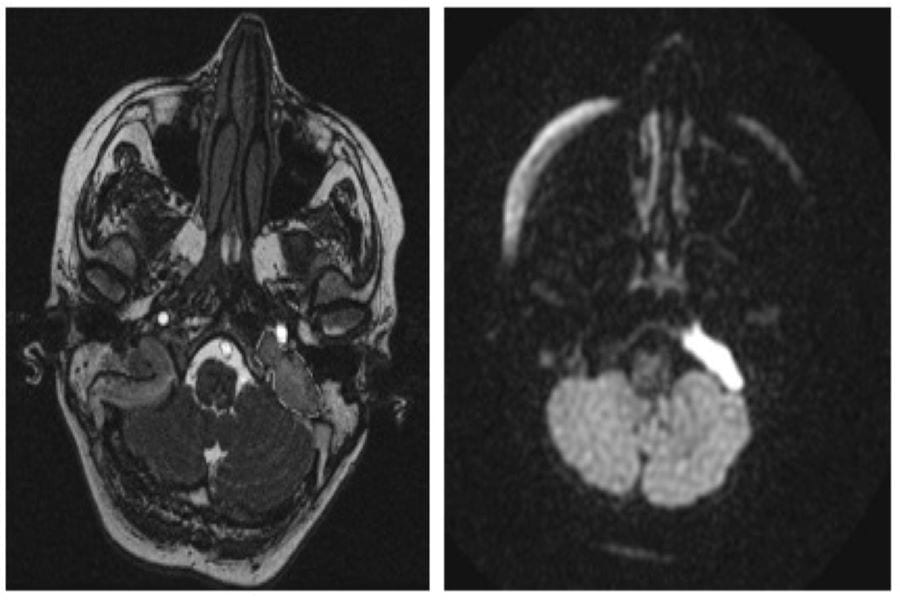

Врачи больницы Мечникова с помощью современных инструментов успешно осуществили сложное хирургическое вмешательство для устранения патологии головного мозга, а именно —

холестероловой гранулемы верхушки пирамиды височной кости.

Женщина 43-х лет поступила с жалобой на двоение в глазах при взгляде влево. При диагностике у нее обнаружили холестероловую гранулему верхушки пирамиды височной кости. По словам Никиты, такое новообразование — вызов для нейрохирурга.

Операцию успешно провел профессор Андрей Сирко на современном нейрохирургическом оборудовании. Благодаря наличию нейронавигации «BrainLab» и операционного микроскопа «Carl Zeiss Opmi Vario 700» стало возможным проведение открытого оперативного лечения в объеме «передняя петрозектомия с удалением ХГ верхушки пирамиды височной кости».

Пациентка чувствует себя хорошо. Уже на второй день после операции у нее улучшились движения глазных яблок.